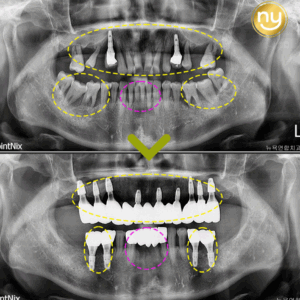

울산안아픈치과 신경치료 후 염증 치아재식술로 해결해요! 안녕하세요. 울산안아픈치과 뉴욕연합치과입니다. 임플란트가 워낙 보편화되고 선호하는 분들이 많아지고 있지만, 자연치아를 살리고자 하는 수요도 급상승하고 있는 추세입니다. 위 환자분은 충치가 많이 진행되어 신경치료한 치아를 사용하고 있었습니다. 하지만, 오랜 기간이 지나 치아 뿌리 끝에 염증이 생겨 발치를 권유받았는데요, 발치를 하더라도 치아 뿌리만 손상 더보기…